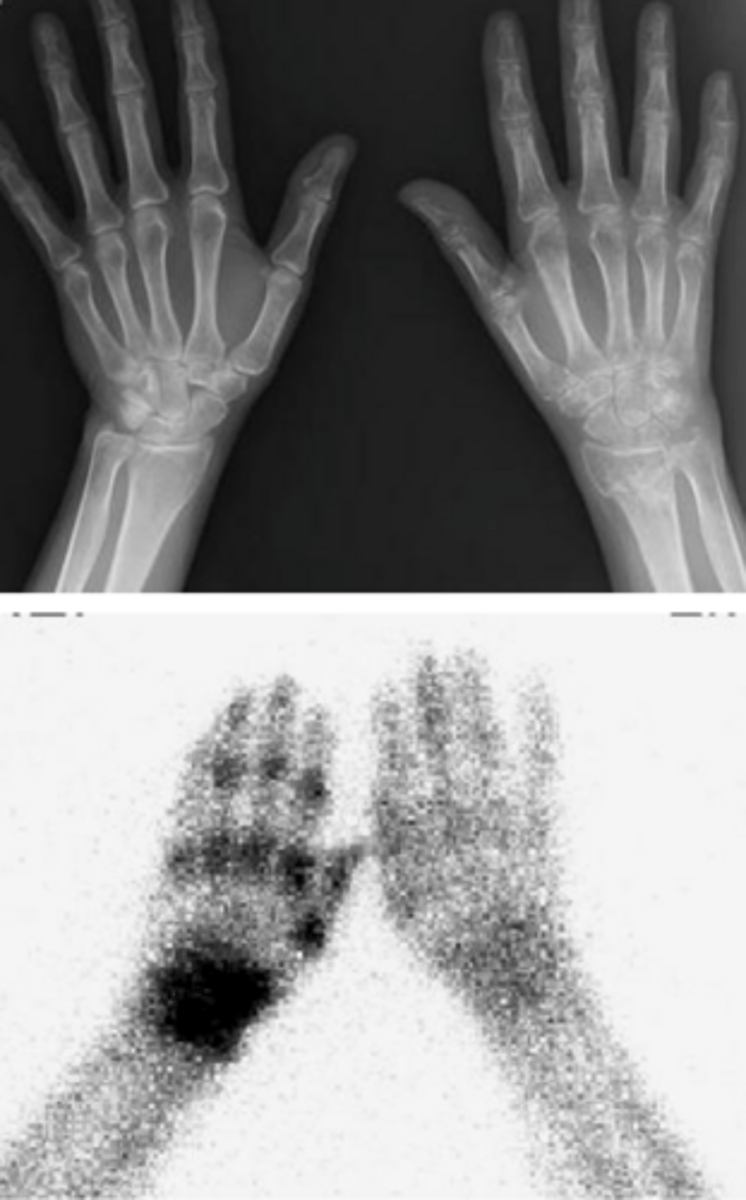

What characterizes the pathophysiology of Complex Regional Pain Syndrome (CRPS)?

Peripheral and central sensitization following injury, which activates an abnormal sympathetic reflex and lowers the pain threshold.

hyperalgesia, allodynia, weakness, decreased movement, skin color and temperature changes

What are the trophic changes commonly observed in chronic CRPS?

Increased hair growth, altered nail growth, skin atrophy, and joint contraction/fibrosis.

What is the typical presentation of CRPS Stage 1 (weeks after injury)?

Pain at the injury site, localized edema, altered color/temperature (bright red, warm), and increased diaphoresis.

What is the typical presentation of CRPS Stage 2 (3-6 months)?

increased edema, brawniess of skin, cool/diaphoretic, and muscle wasting

What is the typical presentation of CRPS Stage 3 (chronic)?

limited movement, digit contracture, waxy trophic skin, brittle nails, demineralization of bone

what is seen on imaging in CRPS?

Bone scan showing diffuse increased uptake in affected extremity or x-ray showing generalized osteopenia